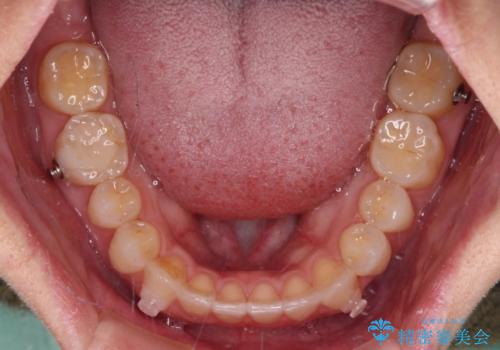

【モニター】狭い上顎歯列とオープンバイト 急速拡大装置を用いた矯正治療

- 前歯の開咬を気にして来院された患者様です。

上顎歯列が狭窄していたため、急速拡大装置により上顎骨を側方に拡大し、その後インビザラインにて矯正治療を行うこととしました。

舌の突出癖が開咬の原因であったので、改善のための舌トレーニングを行っていただきました。

舌トレーニングは後戻りにも大きく影響するため、とても重要なトレーニングです。